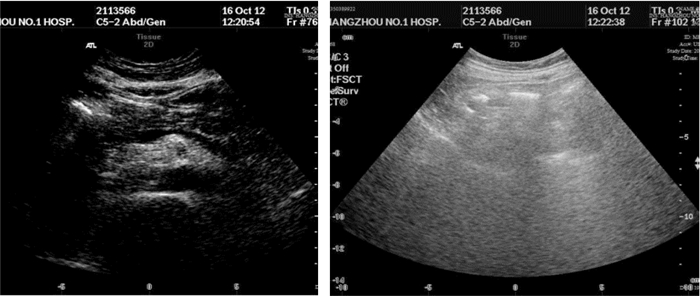

1 病例资料患者,女,64岁,因“反复膝关节疼痛伴腹胀全身肿胀2月余”入院。患者2个月前反复膝关节疼痛后渐出现腹痛腹胀及全身肿胀,及胸闷气急。10 d前至当地医院诊治,给予抗感染、抑酸,营养支持等对症治疗。患者症状无明显好转,遂至本院急诊。既往行“胆囊切除术”后2年,“鼻息肉切除术”后7个月。查体:BP 139/72 mmHg,P:88次/min,R:25次/min,T:37.5 ℃。嗜睡,精神软,口唇无发绀,皮肤干粗糙,巩膜无黄染,全身浅表淋巴结未触及肿大;两肺呼吸低,未闻及干湿性啰音;心率58次/min,律齐,心音低,未闻及病理性杂音;腹膨隆,未见腹壁静脉曲张,腹部可见一长约10 cm手术疤痕,愈合好。未见胃肠型,全腹,左下腹压痛、反跳痛,肝脾触诊不满意,麦式点无压痛,肠鸣音1次/分,腹部移动性浊音阳性;全身浮肿;生理反射存在,病理反射未引出。辅助检查:2012.9.5 肝功(本院):总蛋白 53.2 g/L,白蛋白 24 g/L,尿素 18.41 mmol/L,肌酐 154 μmol/L,血糖 8.74 mmol/L。2012.9.5急诊血常规白细胞 20.6×109/L,中性粒细胞 81.6%,血红蛋白 69 g/L,血小板 22×109/L 。急诊血气分析:pH 7.360,二氧化碳分压. 29.0 mmHg,氧分压. 126.0 mmHg,剩余碱.-8.0 mmol/L;2012.8.28 CT(当地医院)示:两侧胸腔积液伴两下肺压迫性肺不张,心包少量积液,腹腔盆腔积液,肝脏密度不均匀,脾脏增大(图 1,图 2)。2012.8.29 B超(当地医院)示:腹腔积液,双侧胸腔积液(图 3,图 4)。血补体C3 0.472 g/L(0.85~1.93),补体C4 0.077 g/L(0.12~0.36);血T3 0.28 μg/L(0.61~0.81),T4 13.60 μg/L (45~109),FT3 0.70 pmol/L(3.5~6.5),FT4 5.38 pmol/L(11.5~22.7)TSH6.67(0.35~5.50) TPOAb、TgAb阳性;血C-反应蛋白 36 mg/L;腹水外观血性混浊 李凡氏试验(+) 中心粒20 淋巴细胞50间皮细胞25,蛋白35 g/L,CA125 123 U/mL;风湿免疫功能:ANA,SCL-70,JO-1,U1RNP,SM,SS-A,SS-B,组蛋白抗体,抗线粒体抗体,抗PCNA抗体,板层素抗体,抗肌动蛋白抗体,着丝点抗体,抗核小体抗体,均阴性;凝血全套正常;结核抗体阴性;肿瘤指标CA125 512 U/mL。入院诊断为:原发性甲状腺功能减退、多浆膜腔积液。口服左甲状腺素片50 μg/d为初始剂量,以后逐渐增至150 μg/d,泼尼松5 mg早8:00、晚16:00 口服,患者3 d后食欲好转,查头颅MRI及血垂体功能检测正常,排除继发性甲减,停用泼尼松。半月后浮肿消退,至住院1月复查CA125 20 U/mL;B超:心包积液及双侧胸膜腔积液完全吸收,腹腔少量液性暗区。住院40 d复查甲功正常;B超:肝肾隐窝、脾周及腹腔内均未见游离液性暗区(图 4),临床痊愈,出院,出院后服用左甲状腺素片150 μg/d,定期随访,目前以此剂量维持。

| 图 3 治疗40 d后B超:无胸腹腔积液 |